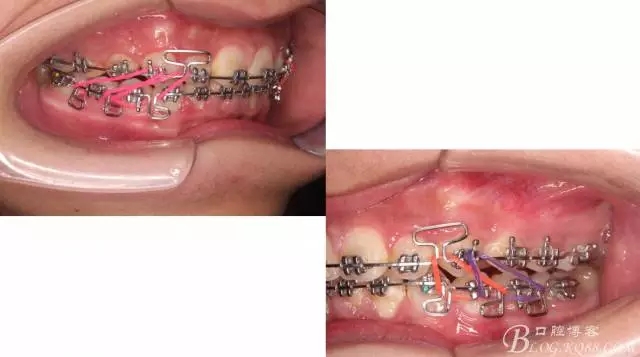

下頜配合多曲方絲,三角牽引,調(diào)整咬合。

中線不齊,咋辦?繼續(xù)哄哄患者配合,2牽+斜牽。

努力沒有白費,中線基本對齊!